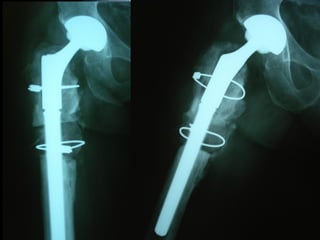

Paprosky 2B

F.U 5 aa